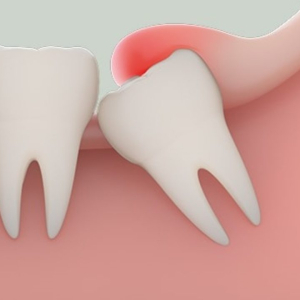

Khi nào cần nhổ răng khôn? Dấu hiệu răng khôn mọc lệch, mọc ngầm

Răng khôn mọc lệch: Dấu hiệu, nguyên nhân, cách xử lý